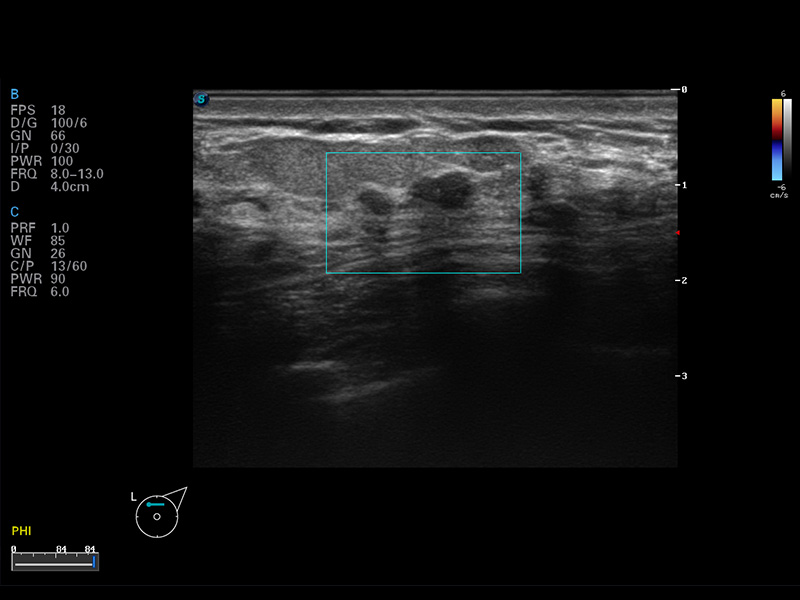

S8 EXP便携式彩色多普勒超声诊断仪是亚星官网研发的高端全身应用型便携彩超。高通道的VIS平台融合可视化(Visual)、智能化(Intelligent)和人性化(Smart)的特点,配以亚星官网自主研发生产的探头大家族,使您能够快速、准确的获得病人信息,提高工作效率的同时减轻疲劳。

μ-Scan微米成像

实时宽景成像